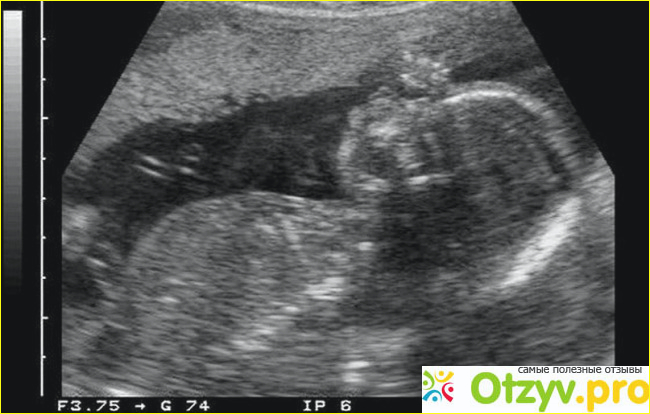

Мини-аборт делается на сроке до 5-6 недель. Все происходит в женской консультации, без госпитализации и уже через пару часов женщина может идти домой.

Аборт возможен и на более поздних сроках, но уже только по медицинским показаниям или в особых случаях. Проводится такой аборт на сроке до 21 недели. Дальше - это уже искусственные роды, ведь плод сформировался и даже может выжить.